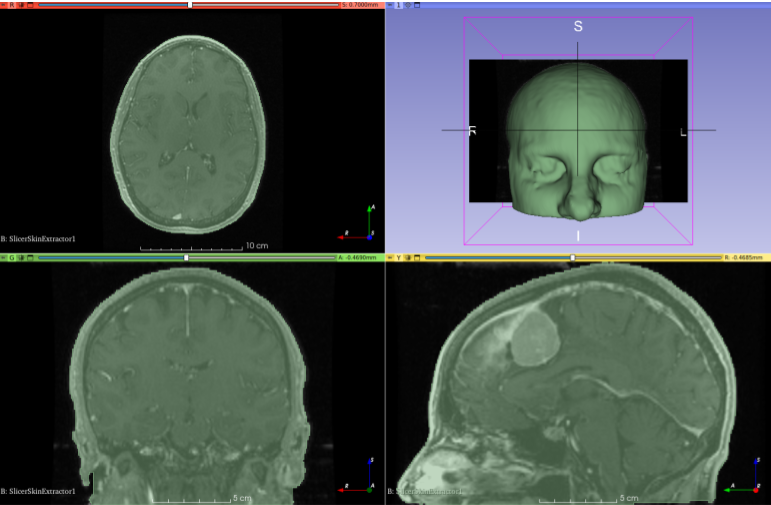

Illustrations